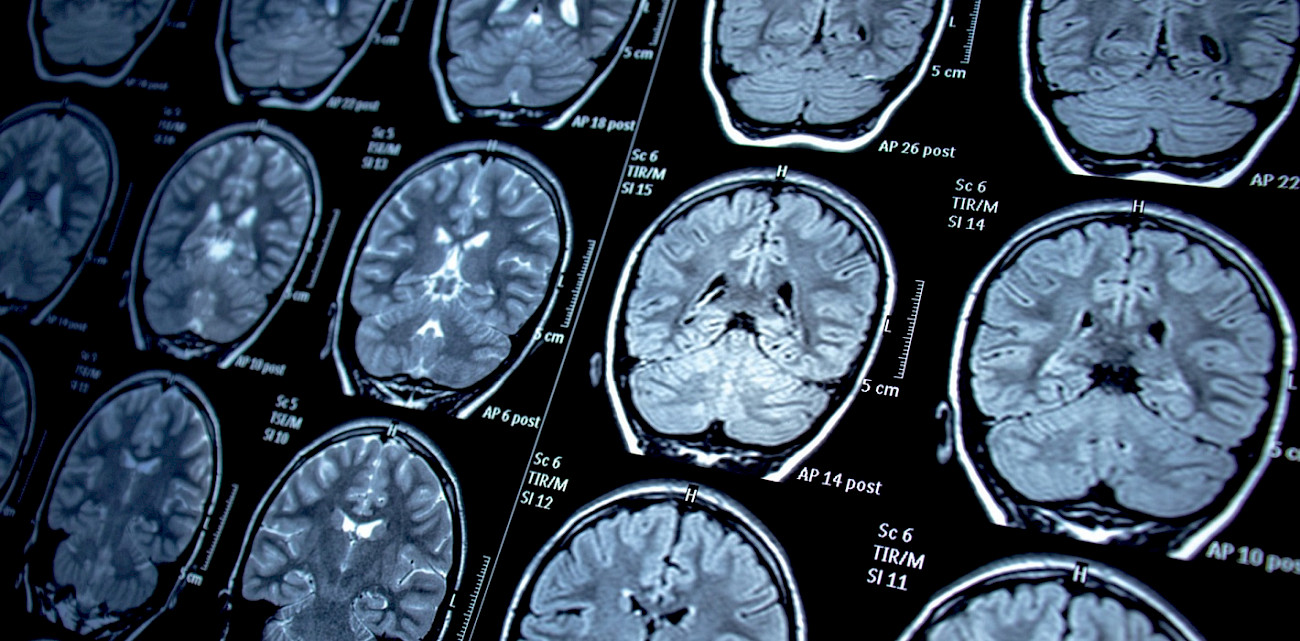

Irm

Neurologie

Neurochirurgie